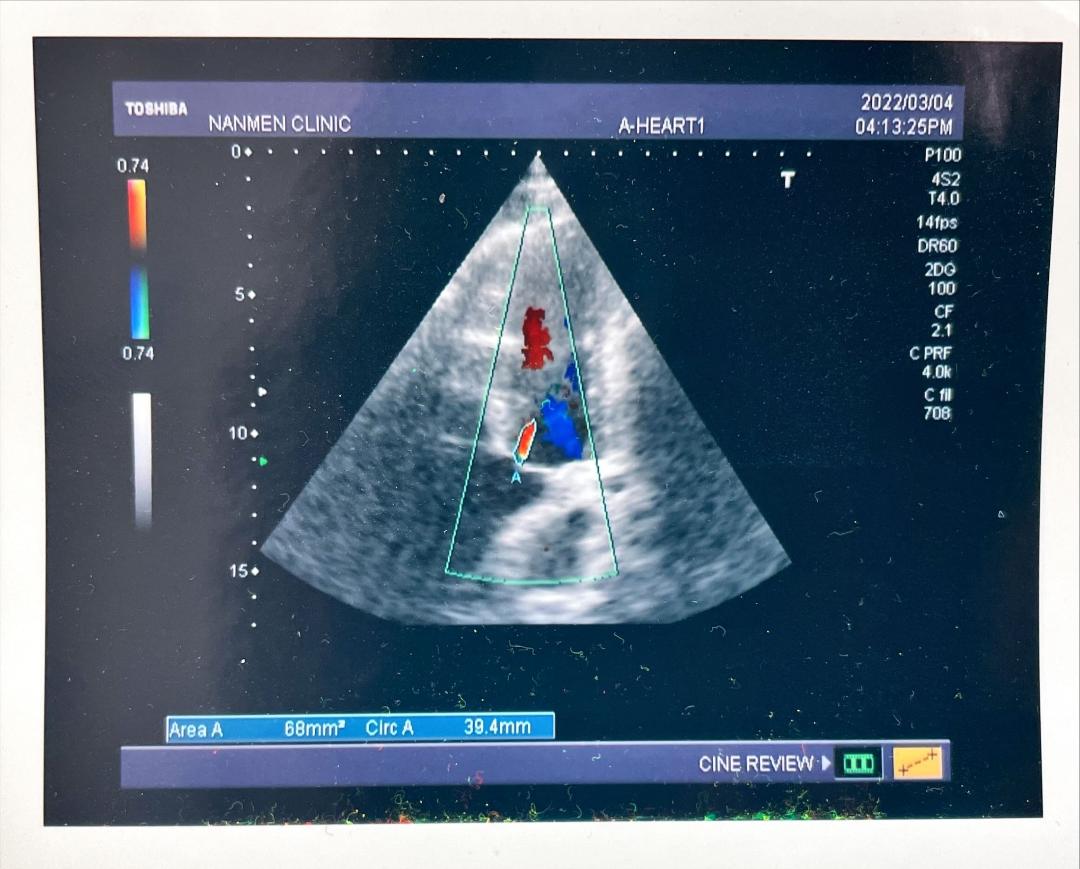

一、心臟超音波檢查:

心臟超音波檢查可進行心臟結構和功能的評估,瞭解心臟的大小、收縮情形,判斷心臟瓣膜活動的情況。彩色超音波及杜卜勒血流測定可判別心臟血管內的血流方向及流速還可偵測是否有心臟瓣膜缺損,提供民眾心血管功能檢查的診斷與評估。